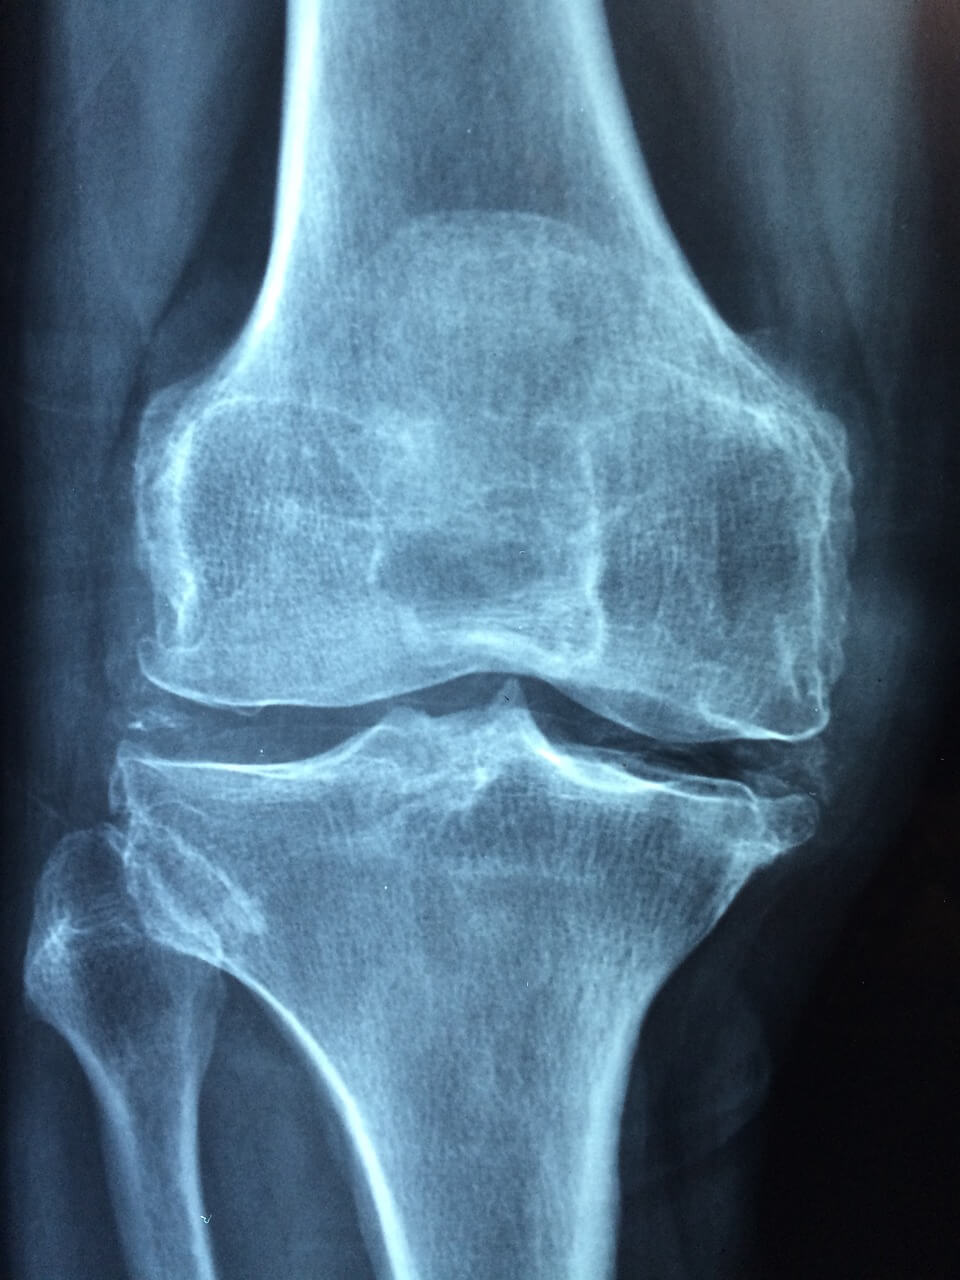

콘드로이친(Chondroitin)은 연골에 존재하는 다당류 성분으로, 관절 내 연골의 마찰을 줄이고 충격 흡수와 유연성 유지에 중요한 역할을 합니다. 이 중에서도 Chondroitin-6-Sulfate(C6S)는 콘드로이친 계열 중에서도 체내 흡수율이 높고 생물학적 활성이 뛰어난 형태로, 특히 철갑상어에서 추출한 C6S는 고순도, 고활성의 특징으로 주목받고 있습니다.

C6S는 관절 내 활액의 점성을 높이고, 윤활 작용을 촉진함으로써 연골 마모를 방지합니다. 염증성 사이토카인(IL-1β, TNF-α 등)을 억제함으로써 관절통, 뻣뻣함, 부기 등 다양한 관절 증상의 개선에 도움을 줍니다.

철갑상어 콘드로이친은 연골세포의 분화와 증식을 촉진해 손상된 연골의 회복을 지원합니다. 퇴행성 관절염, 슬개골 연골연화증 등 노화성 질환의 진행을 늦추는 효과도 입증되고 있습니다.